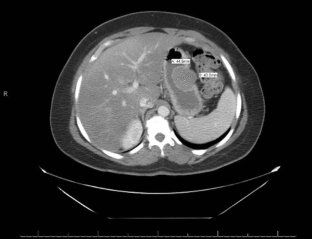

• Gastrointestinal stromal tumors (GISTs) are uncommon intramural tumors of the GI tract. They are most often seen in the stomach and arise from the muscular layers of the visceral wall.

• The clinical manifestations of GISTs vary depending on the tumor size and location, but are often asymptomatic.

• Advances in endosonography (EUS) and immunohistochemical staining can distinguish these lesions from other intramural and GI tract tumors and are an essential part of the diagnostic and staging workup.

• The cases presented in this report represent pathology-confirmed GISTs diagnosed at a large volume, community, tertiary referral GI oncology program during July 2012 through May 2016. Follow-ups for each patient have discovered no recurrences to date.